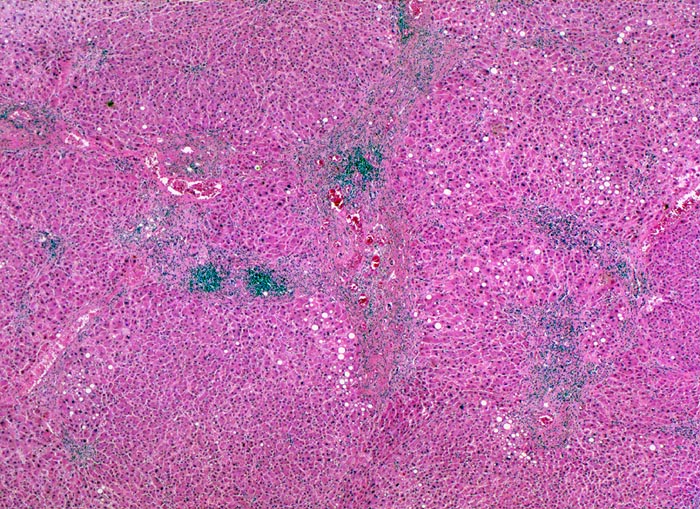

Makroskopisch imponiert das hepatozelluläre Karzinom als solitäre grosse Tumormasse, als zahlreiche zirrhoseartige Knoten oder als scharf begrenzter Knoten mit oder ohne Kapsel. Die tumorfreie Leber ist in der Mehrheit der Fälle zirrhotisch umgebaut. Mikroskopisch bilden die Tumorzellen mehr als 2 Zellen breite Trabekel (> 1237), kompakte Tumormassen (> 1229) oder pseudoglanduläre Strukturen (dilatierte Canaliculi) (> 1212) (> 1199). Desmoplastisches Bindegewebe fehlt meist. Innerhalb des Tumors fehlen Portalfelder. Es finden sich lediglich Arterien. Etwa bei der Hälfte der Karzinome lässt sich intrazytoplasmatische oder intracanaliculäre Galle (> 1238) nachweisen. Immunhistochemisch lassen sich mit einem polyklonalen Antikörper gegen Carcinoembryonales Antigen (CEA) Gallecanaliculi zwischen den Tumorzellen nachweisen. Die Tumorzellen bilden keinen Schleim.

• Innerhalb des Tumors Blutgefässe, aber keine Portalfelder.

• Die Tumorzellen bilden Trabekel, welche überwiegend mehr als 2 Zellen breit sind und Pseudodrüsen.

• Sinusoidartige Blutgefässe mit Endothelauskleidung verlaufen zwischen den Trabekeln und den Pseudodrüsen.

Geringe gemischttropfige Verfettung des Leberparenchyms.